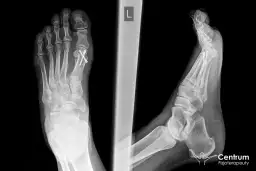

Po upływie sześciu tygodni od operacji, codzienne aktywności zazwyczaj nie powinny wiązać się z odczuwaniem bólu. Po potwierdzeniu prawidłowego zrostu kostnego na zdjęciu rentgenowskim, pacjent może stopniowo wracać do noszenia normalnego obuwia i pełnego obciążania stopy. Warto jednak pamiętać, że po bardziej intensywnym wysiłku, dolegliwości mogą jeszcze sporadycznie powracać.

Przez około sześć tygodni po operacji pacjent porusza się przy pomocy kul i nosi specjalny but pooperacyjny, który odciąża operowaną stopę. Po tym okresie, jeśli zdjęcie RTG potwierdzi prawidłowy zrost kostny, można stopniowo zacząć nosić normalne obuwie i w pełni obciążać stopę. Początkowo chodzenie może być jeszcze nieco niepewne, a ból może pojawić się po dłuższym wysiłku, ale z każdym dniem powinno być coraz łatwiej.